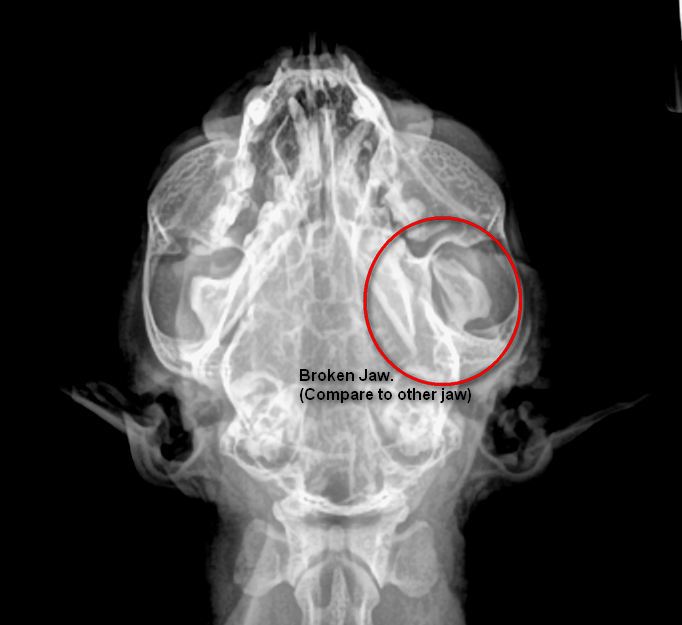

Can You Fix A Cat's Broken Jaw . In healthy cats and dogs, a large force (trauma) is required to fracture the mandible (lower jaw). A fracture is a break in the bone and can range in severity from a greenstick (incomplete crack). Any type of feline fractures warrant. Is my cat's jaw broken? This is a device that is relatively easy to apply and helps to fix the cats jaw in place to allow the fracture to heal. Learn about the treatment process involving wiring the jaw back together and the. Learn what causes this problem, how to tell if your cat has a broken jaw, and how to treat it. Discover how we diagnose and repair cat lower jaw fractures. The upper jaw bones are called the maxilla and the lower jaw bones are called the mandibles. Upper and lower jaw fractures generally happen when a cat’s jaw is subjected to blunt force or trauma.